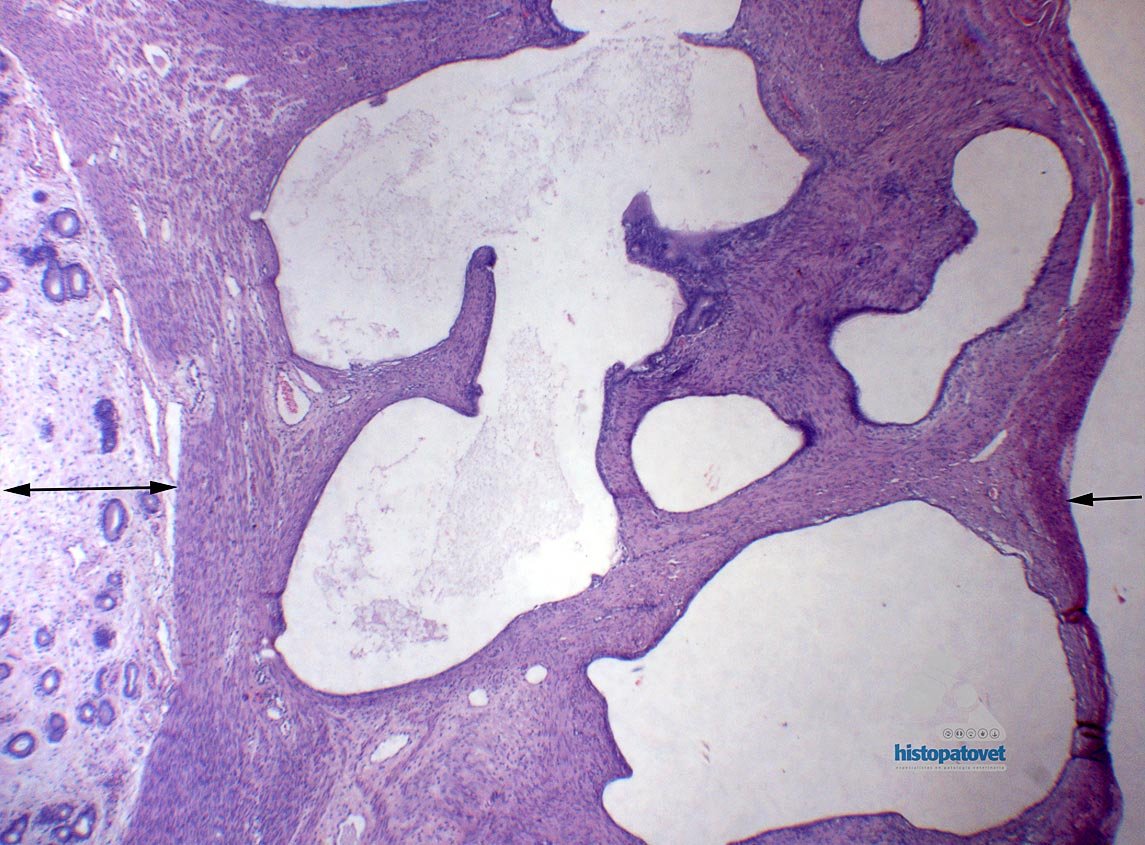

B. Examen microscópico: En la submucosa o miometrio se observa la formación de múltiples cavidades, algunas de ellas vacías, otras con un contenido levemente proteico. Las cavidades a su vez están revestidas por una monocapa de células cúbicas, algunas de ellas están atróficas. Fig.4.

Fig.4. La flecha con doble punta (izquierda), muestra una pequeña porción de la mucosa. La de la derecha, indica la serosa. En medio de ambas flechas esta el miometrio con varias cavidades vacías.